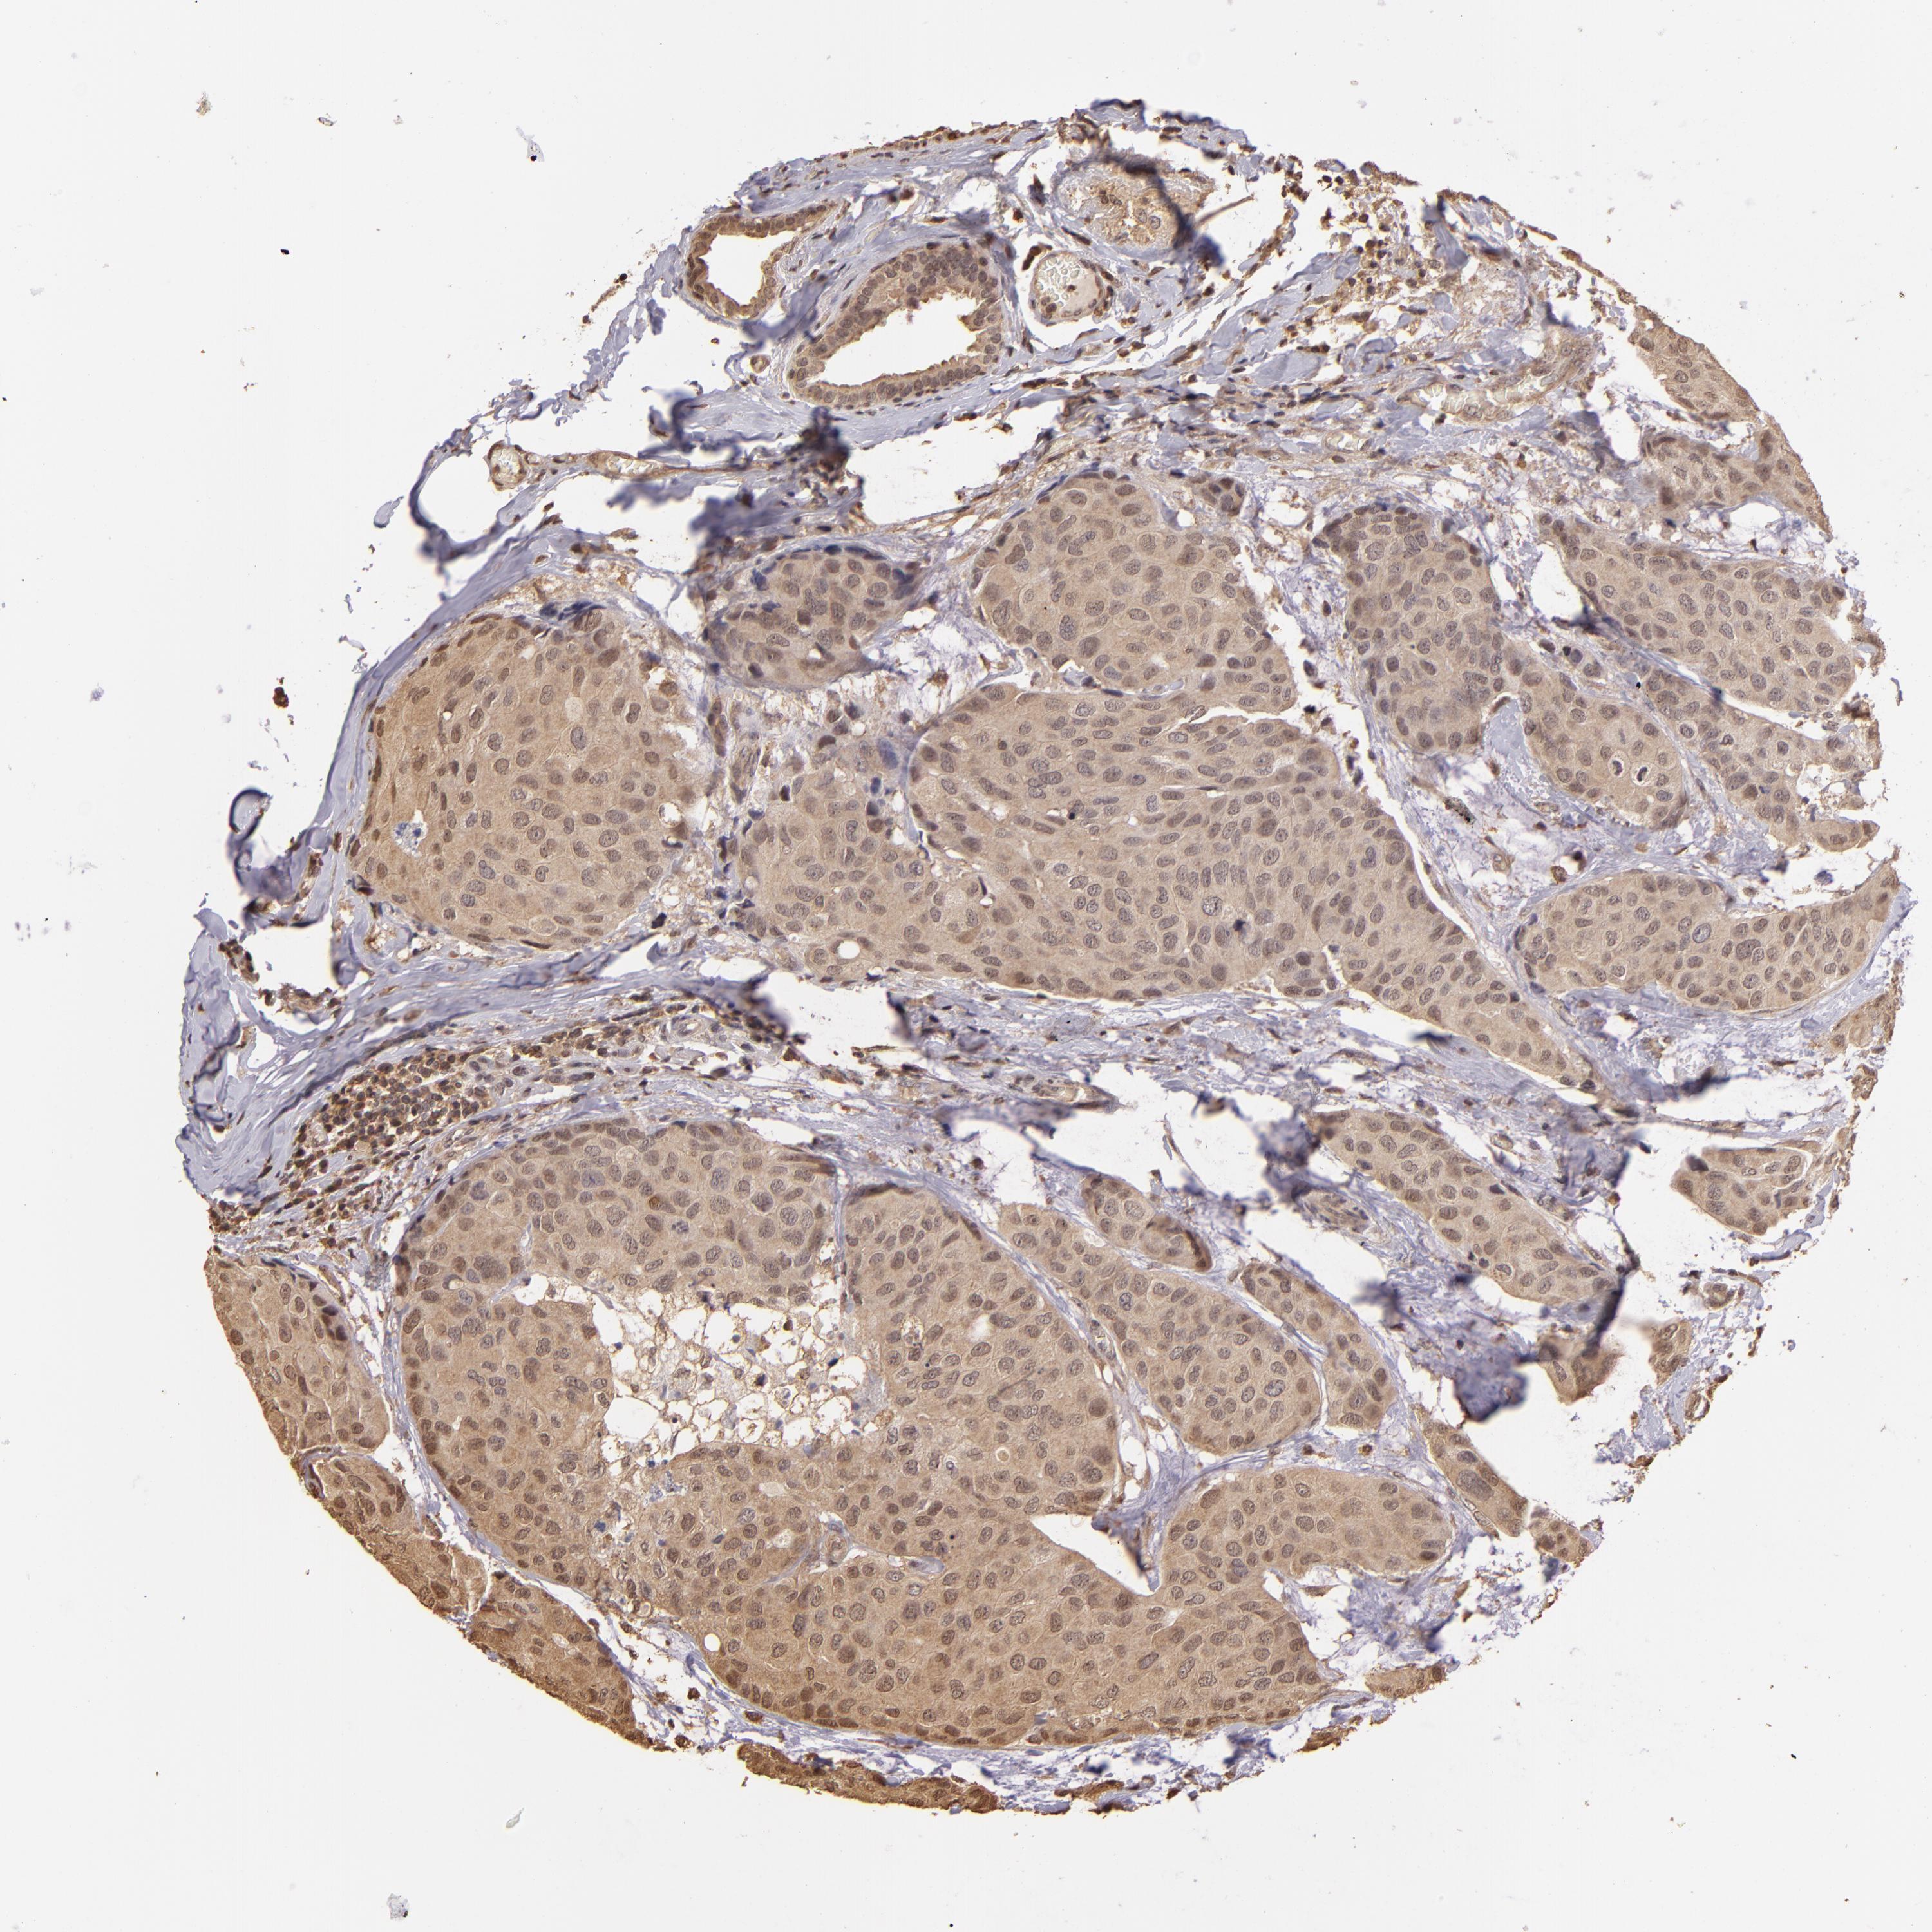

BRCA TCGA BRCA VALIDATION PROTEIN EXPRESSION

Breast cancer

Human cancer